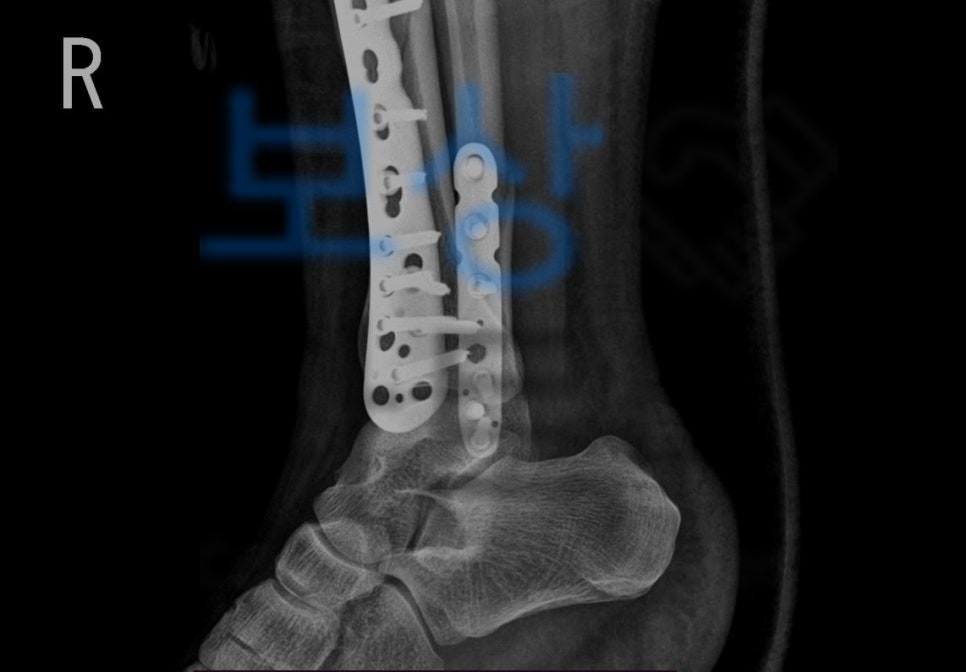

위처럼 골절의 정도가 심각하여 금속으로 고정하여야 하였습니다. 골절진단비, 실비, 수술비는 보험사에서 요청하는 대로 진단서나 영수증을 받아 청구하시기만 해도 받으십니다. 하지만 저희가 소개해드릴 보험금은

의뢰인은 족관절 기능에 대한 **약간의 장해 5%**에 해당하셨습니다. 저희는 위 발급된 장애 진단서를 기초로 손해사정서와 증빙서류를 보험사에 송부하였고

물론 보험사에서는 내부 심사를 진행하여 약간의 장해 역시도 한시장해라고 주장했지만 보상 파트너의 적절한 대응으로! 5% 지급률 영구 장해로 인정받아!